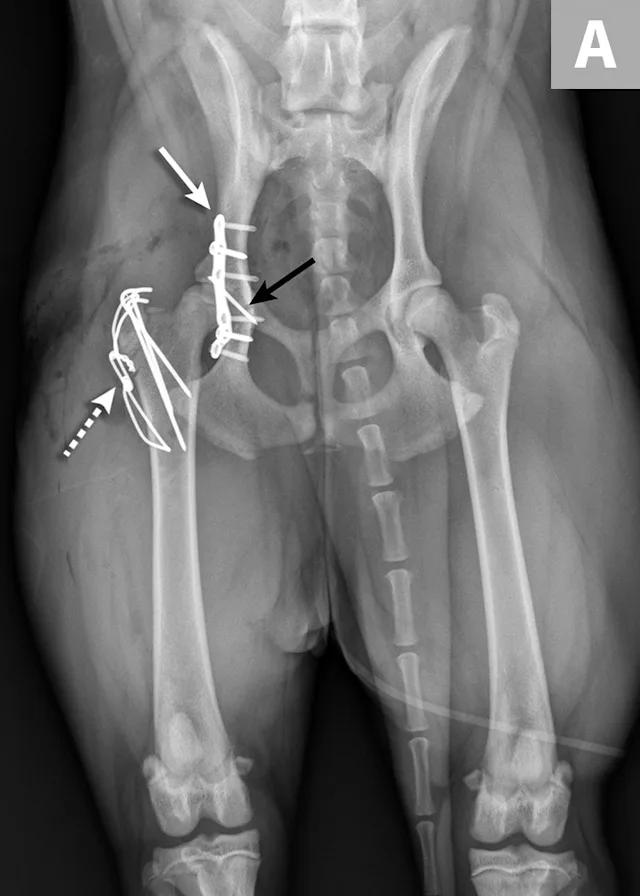

FIGURE 4A

Postoperative ventrodorsal (A) and lateral (B) projection images of the same dog in Figure 2. Fracture reduction was achieved with cross pins and a figure-eight hemicerclage wire (black arrows). Reduction was protected via application of a locking string-of-pearls neutralization plate (solid white arrows). To gain access to the full extent of the fracture, a greater trochanteric osteotomy was performed and stabilized with a positional screw and pin (dashed arrows). The ventrodorsal postoperative radiograph revealed a sacral fracture not previously appreciated (arrowhead). The fracture was successfully treated with conservative management.

Sacroiliac luxation and sacral fracture are the most common causes of multiple neurologic deficits in pelvic injuries3 and are caused by the location of the lumbosacral plexus ventral to the sacrum. Surgery for sacroiliac luxation depends on several factors, including degree of displacement, bilateral injury, and level of discomfort.21-23 Lag screw placement traversing >60% of the width of the sacrum is the most common surgical technique used for sacroiliac luxation.24,25

Ilial fracture stabilization can be accomplished using several methods individually or in combination; lateral or ventral plate stabilization with locking or nonlocking plates are the most common methods. Sciatic nerve injury can be associated with ilial fracture because of the location of the nerve medial to the ilial body. Care should be taken during fracture reduction and stabilization to avoid iatrogenic trauma to the nerve.26

Most acetabular fractures have traditionally been treated surgically; however, it has been suggested that fractures in the middle to caudal third of the acetabulum can be treated conservatively.3,5,7,13,25,27 Precise reconstruction of the acetabulum is needed for acetabular fracture repair.3,7 Surgical access to the acetabulum requires osteotomy of the greater trochanter to achieve proper exposure. Two- and three-part fractures are most amenable to reconstruction. Stabilization is most commonly achieved via plating, but other techniques have also been described.3,5,7 Femoral head and neck ostectomy is an option for comminuted acetabular fractures or injuries resulting in severe cartilage damage to either the femoral head or acetabulum.3,7